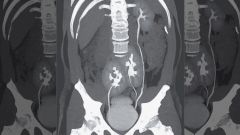

Сложную пересадку печени провели в Научно-исследовательском институте скорой помощи им. Н. В. Склифосовского. Из-за тяжелого заболевания родной орган россиянки стал отказывать.